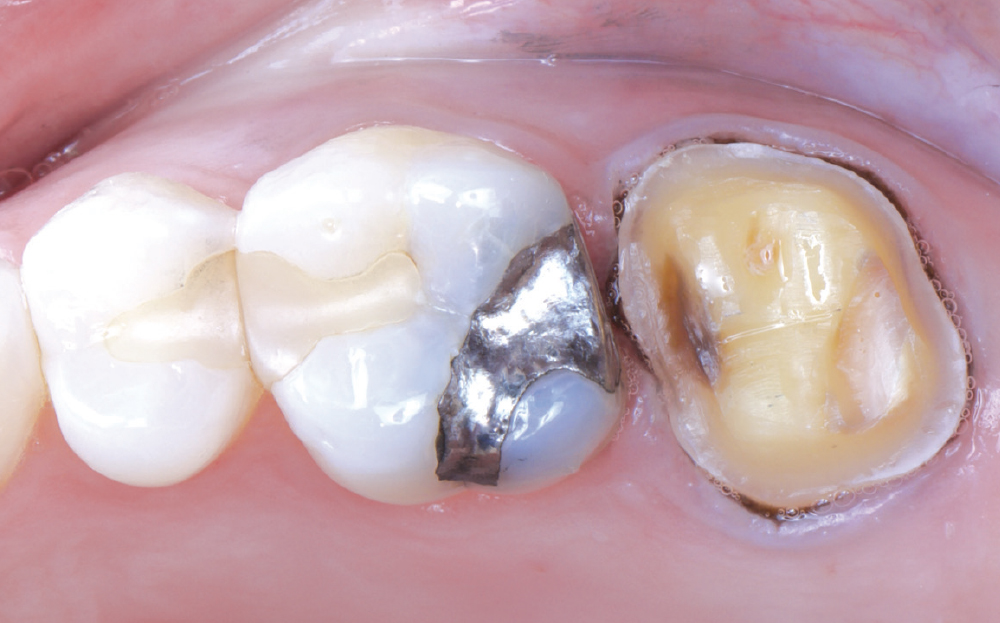

The patient’s chief concern was an open mesial margin of the crown on tooth #15

Figure 1: The patient’s chief concern was an open mesial margin of the crown on tooth #15, which was causing gingival inflammation and shredding her dental floss.

The crown was a 20-year-old Captek™ PFG high-noble bilayered restoration

Figure 2: The crown was a 20-year-old Captek PFG high-noble bilayered restoration.